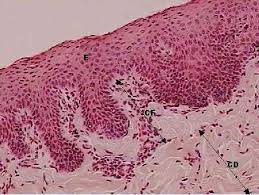

Vamos falar sobre a Matriz Extra Celular – MEC, e quais são os riscos para o desenvolvimento das inflamações, bem como o processo de recuperação da MEC.